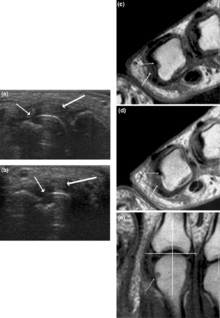

Other medical imaging techniques such as magnetic resonance imaging (MRI) and ultrasound are also used in RA.[14]

There have been technical advances in ultrasonography. High-frequency transducers (10 MHz or higher) have improved the spatial resolution of ultrasound images; these images can depict 20% more erosions than conventional radiography. Also, color Doppler and power Doppler ultrasound, which show vascular signals of active synovitis depending on the degree of inflammation, are useful in assessing synovial inflammation. This is important, since in the early stages of RA, the synovium is primarily affected, and synovitis seems to be the best predictive marker of future joint damage.[48]